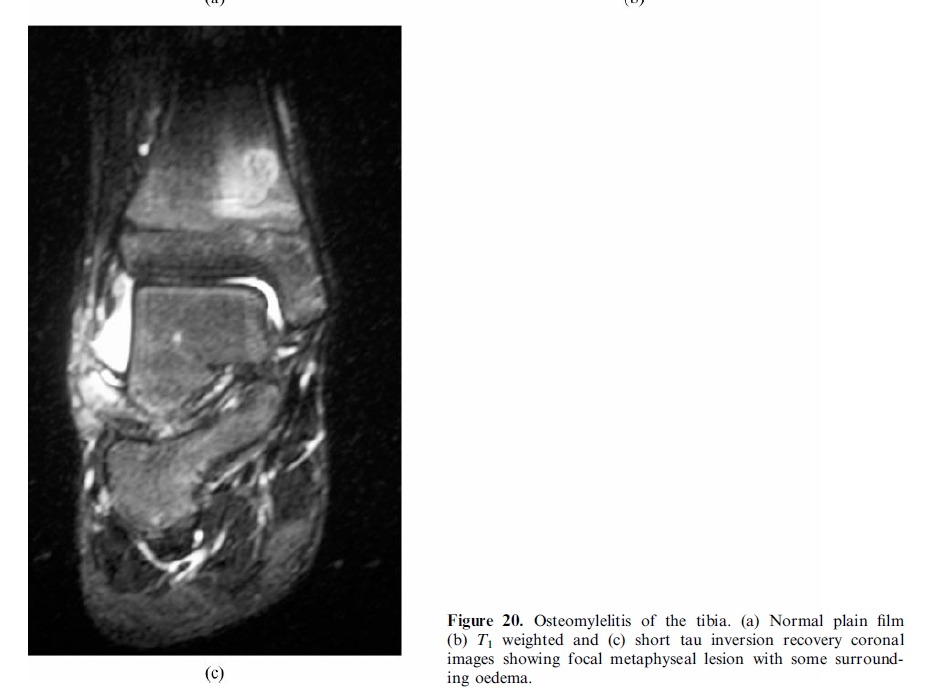

# MRI is the most suitable technique for global assessment of bone and soft tissues for persistent pain following injury.